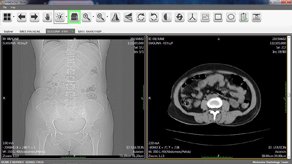

Brand new Workstation for all your radiology needs.

Intelligence lenses on screen to read all images.

World class Kins PACS system with affordable cost.

Art of imaging with proven idea to increase care on patient and revenue.